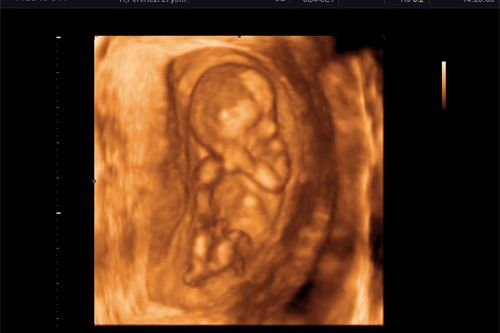

Rendelőnkben a legmodernebb technikával, a Medison SonoAceX8-as készülékkel végezzük a csecsemők és gyermekek ultrahangos vizsgálatát. Ez egy korszerű, nagy felbontású gép, így lehetőség van az apróbb részletek megjelenítésére, a fontos ultrahangos vizsgálatok elvégzésére.